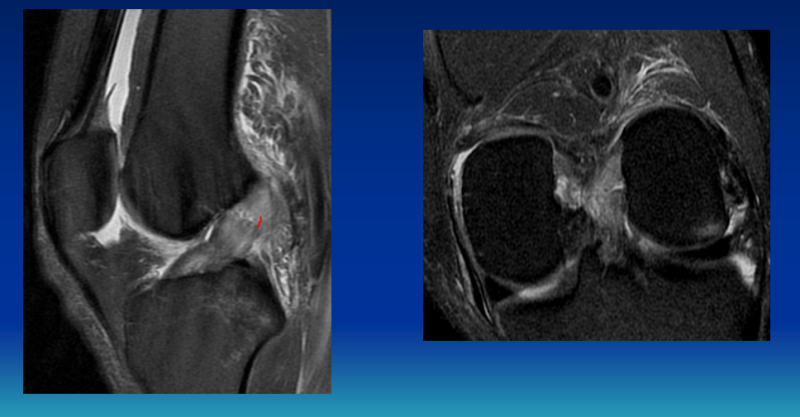

무릎관절은 대퇴골, 경골, 슬개골 등 3개의 뼈와 4개의 인대로 구성됩니다. 이 중 십자인대는 무릎관절 내부에 존재하는 십자형(+) 모양의 인대로, 관절의 전·후 움직임을 조절하는 역할을 한다. 앞쪽에 있는 전방십자인대는 경골이 대퇴골 위로 앞으로 미끄러지는 것을 방지하고, 뒤쪽에 있는 후방십자인대는 뒤쪽으로 미끄러지는 것을 방지합니다. 회전 시 관절의 안정성에 중요한 역할을 하기 때문에 십자인대 파열이 발생할 수 있습니다. 무릎이 불안정해지고 퇴행성관절염이 가속화될 수 있으니 주의하세요. 무릎 십자인대 파열의 90% 이상이 외부 충격에 의해 발생한다.

무릎 십자인대가 파열되면 ‘뚝’하는 소리가 나며 극심한 통증과 붓기가 동반된다. 운동 중 태클이나 충돌 등 직접적인 접촉으로 파열되면 바로 일어나 걷기가 어려워지고 불안정성이 발생해 정상적인 보행이 어려워진다. 또한 근육 내부에서 출혈이 발생하고 멍이 들기도 합니다. 그로 인해 다른 질환에 비해 내원 시기가 빠른 편이지만, 3~5일 정도 지나면 통증과 붓기가 다소 완화되어 치료를 하지 않고 방치하는 경우가 많습니다. 그러나 십자인대는 관절의 안정성과 균형감각에 영향을 미치기 때문에 장기간 치료하지 않고 방치할 경우 불안정성이 생기거나 운동범위가 감소될 수 있으므로 주의가 필요합니다. 무릎 인대 파열의 단계와 손상 정도를 고려하여 수술 방법을 결정합니다.

십자인대 파열을 치료할 때는 파열 정도와 활동도도 함께 고려한다. 활동량이 적은 노인이거나 불안정성이 없는 경우에는 수술보다는 약물치료, 주사치료, 물리치료 등 보존적 치료를 통해 염증과 통증을 조절하게 됩니다. 다만, 20~40대의 젊은 연령층에서 발생한 외상성 파열이라면 관절경을 사용할 수 있다. 인대 복구(손상된 인대를 봉합하는 수술) 또는 인대 재건(손상된 인대를 제거하고 새로운 인대를 만드는 수술)이 수행됩니다. 경우에 따라 이식(타인의 인대를 이용하여 봉합)하는 경우도 있으므로 환자의 상태에 맞는 무릎 십자인대 파열 수술법이 필요합니다. 준비운동을 통해 십자인대 파열을 예방하는 것이 최우선입니다.